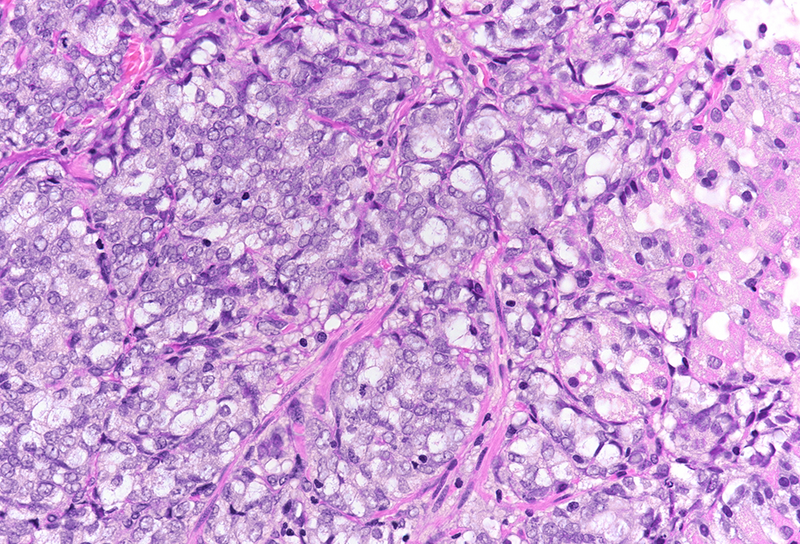

On low power, nodular infiltration of the corpus mucosa by middle-size pale to basophilic tumour cells is seen, arranged in solid nest-like arrangement lacking glandular appearance (Panel C-D). The surface epithelium is not involved, there is no background inflammation, atrophy and/or metaplasia. The tumour cells are positive for pan-keratin, keratin 8/18, however negative for keratins 7 and 20. This peculiar keratin profile prompted staining for Prostate-specific membrane antigen (PSMA, Panel E) and NKX3-1 which is an androgen-regulated, prostate-specific homeobox gene (Panel F). Ultimately, diagnosis of prostate cancer metastatic to the stomach was made.